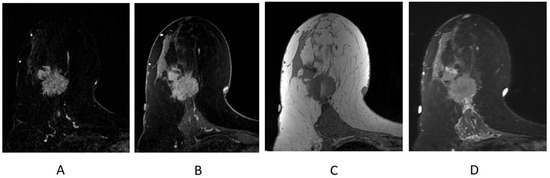

3.2.3. Assessment of Tumor Response after Neoadjuvant Therapy

3.2.4. MR Imaging Response by Molecular Subtype

3.2.5. MR Imaging Response by Imaging Phenotype